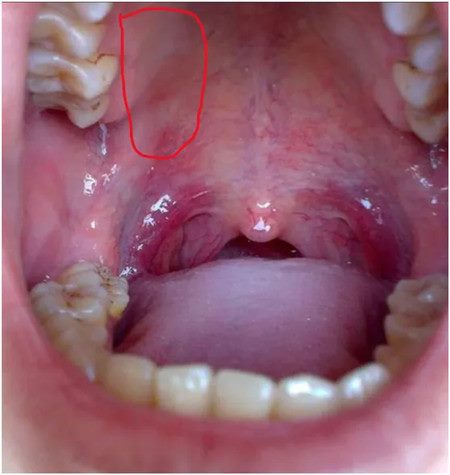

根治:这一次,她的疼痛局限在右侧上牙槽上颚区域,为了更少花费、更小痛苦、更快恢复,神经外科一病区决定利用

这种技术犹如导弹般精准打击造成李阿姨痛苦的神经。在CT引导定位下,进行圆孔穿刺,上颌神经射频治疗。

▲ 术中影像学图片

在寿记新主任的带领下,吴峰副主任医师的协作下,丁攀峰、程森、王冰冰医生在CT室对李阿姨进行了精准的治疗。幸运的是,经过三叉神经第二支射频术的治疗,李阿姨终于能够正常进食和安睡。不仅疼痛消失了,连“胃炎”引起的呕吐也好了,原来呕吐也与神经受刺激的反射有关。